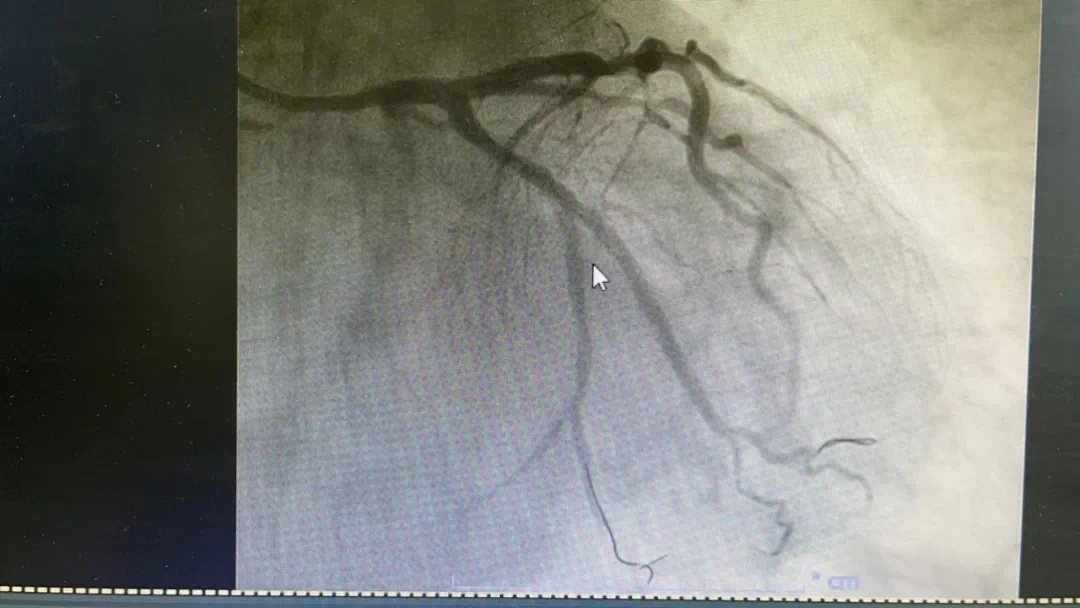

3月4号晚,总医院一个不平凡之夜。19点44分,急诊科汪小卫医生在胸痛中心微信群发送了一条信息:患者程某心电图检查结果。心内科副主任何涛马上回复:患者确诊为急性下壁ST段抬高型心肌梗塞并一键启动导管室,医生熊俊锋、导管室张梅梅立即奔赴导管室穿好铅衣备好急救药品物品,打开除颤仪做好手术准备。19点54分,激活导管室。20点08分患者被送入导管室快速实施冠脉造影,显示患者右冠近段粥样硬化伴“瘤样扩张”,中段发生完全闭塞。结合心电图考虑堵塞血管为右冠,于20点27分成功开通堵塞血管。患者从医院大门到开通血管仅50分钟,大大缩短心肌获得灌注时间,心功能基本不受影响。 术中险象环生,患者心率进行性下降,血压反复异常,经医护人员的及时救治,患者转危为安被安全护送回病房。术前、术后图片如下

术前、术后图片如下